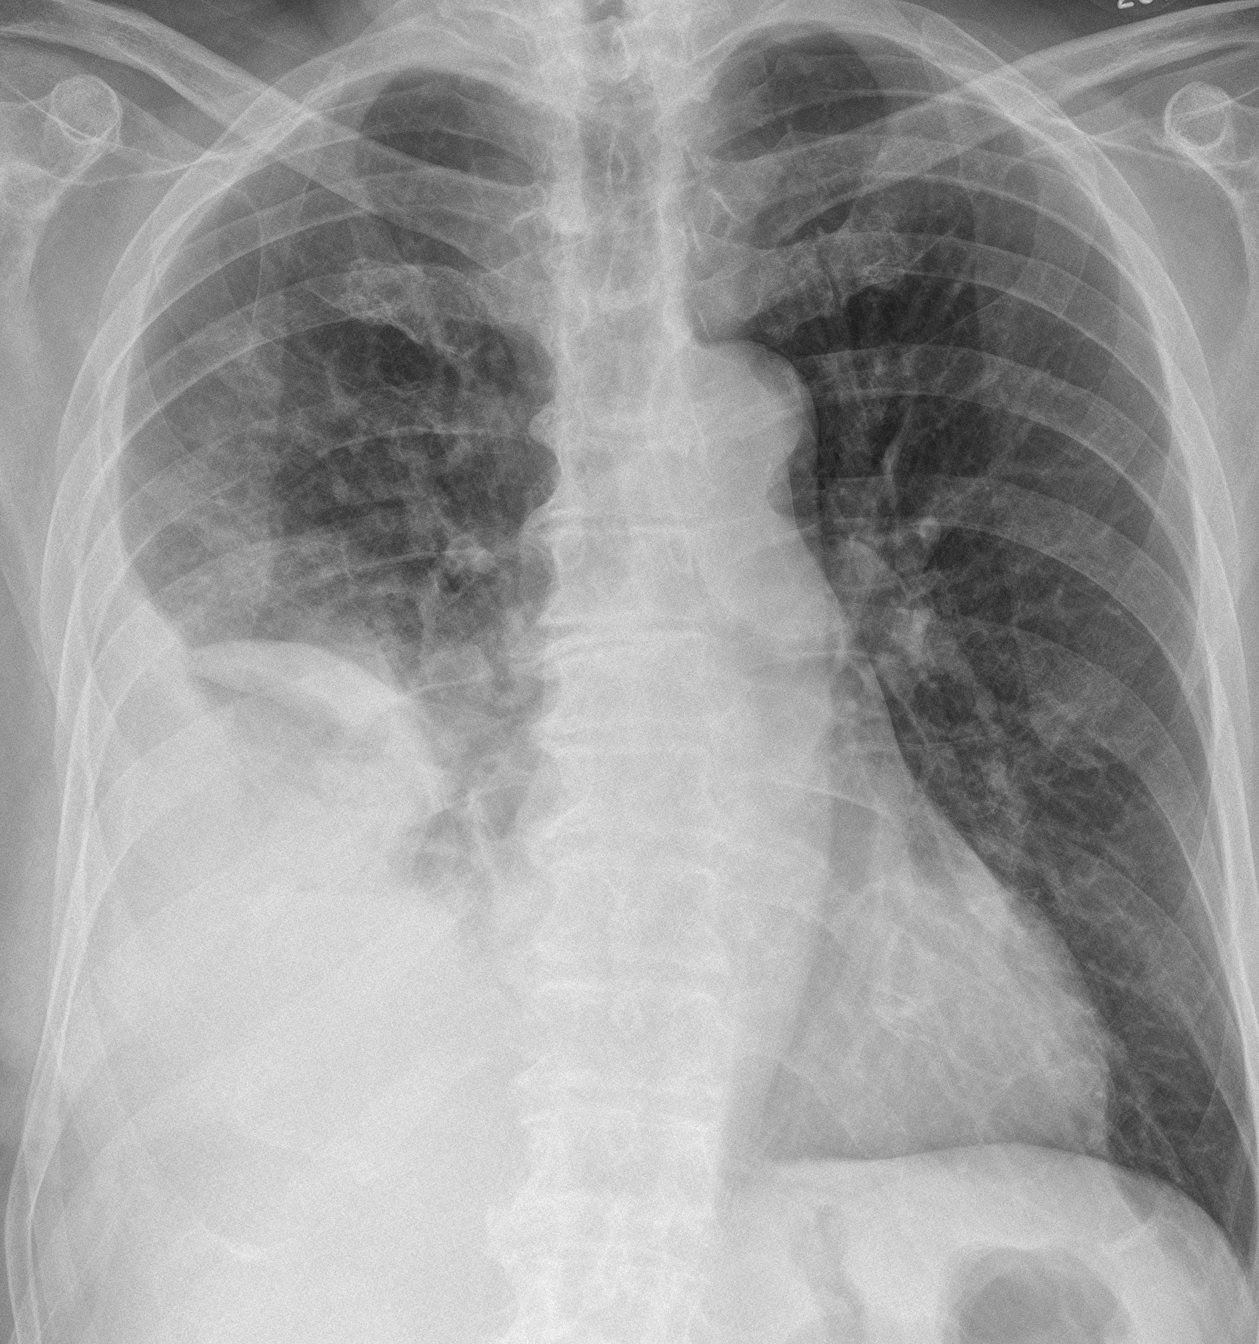

Gallery Pleural Empyema

Empyema